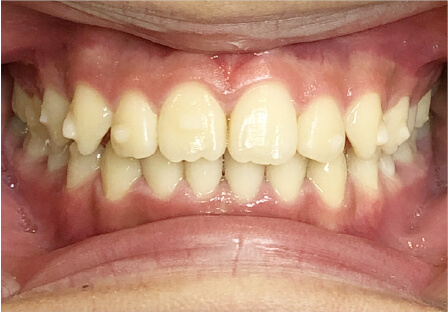

叢生の症例

10歳

/

女性

相談内容

スペース不足

カウンセリング・診断結果

myoからの移行。スペース不足のためインビザライン開始。

治療内容・方法

全額アライナー矯正

術後の経過・現在の様子

クリアライナー使用

治療のリスク

痛み・歯根吸収・歯肉退縮・虫歯・後戻り

費用・治療期間

(インビザのみ)385,000円、1年2ヶ月 + myo3年4ヶ月

トレーニングなど